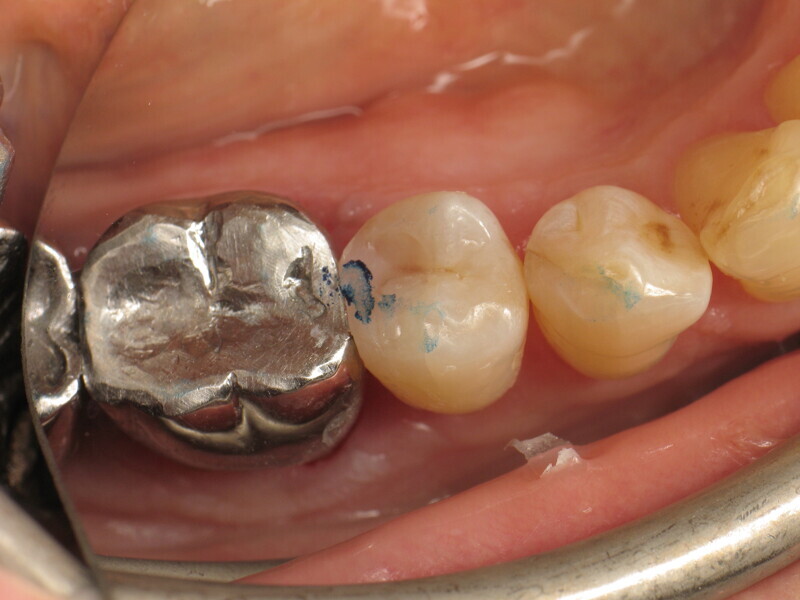

Enfin, une photopolymérisation est réalisée pendant 20 secondes (puissance ≥ 1 000 mW/cm2 ; Fig. 14). Le maquillage est ensuite réalisé avec un composite teinté photopolymérisable (FinalTouch, VOCO, couleur orange, Fig. 15). Après 20 secondes de durcissement du composite de maquillage (Fig. 16), un gel de glycérine est appliqué (Fig. 17) puis la photopolymérisation finale est effectuée (Fig. 18). L’excédent est ensuite retiré et la surface est polie (Fig. 19). Pour ajuster l’occlusion, du papier à articuler est utilisé pour visualiser les points de contact (Fig. 20) et apporter les corrections nécessaires (Fig. 21). Le résultat final est très naturel (Fig. 22).

La patiente était très satisfaite du résultat du traitement et impressionnée par l’esthétique de la restauration, qui se distinguait à peine ou pas du tout de la dent naturelle. De plus, elle pouvait utiliser le fil dentaire sans difficulté particulière.